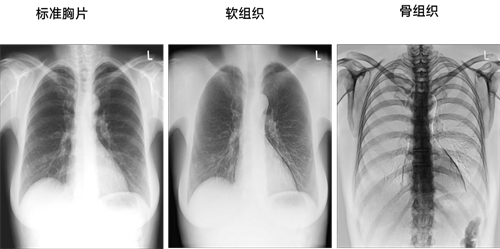

从1895年伦琴发现X线机以来,DR一直受限于二维解剖成像,技术的进展主要在于探测器的进步,核心是从间接化朝着直接化发展,从模拟化到数字化发展,到了21世纪以后,最主要的进展就是非晶硅平板探测器的发明,让DR的数字化水平大幅度提高,平板探测器从2012年全面在全球使用,随后的十年间,数字化X线摄影探测器技术再无进展。

2021年,在探测器领域,安健科技率先向探测器发起挑战,受限于传统探测器的单层闪烁体涂层设计,想要实现双能成像,就需要通过高低KV两次曝光参数条件,来完成能量减影,实现临床需求的双能成像。这个解决方案的弊端,在于需要对患者进行两次摄片,患者需要接受两次剂量辐射。

安健科技探测器技术研发团队,设想了一种基于多层平板探测器的X射线多能成像方法,通过多层闪烁体涂层设计分别吸收不同能量的X光信号,来完成双能影像重建。

放射影像的发展,自诞生之日起,就与科学发现、技术与工程创新密切相关。无论是1895年伦琴发现X射线,还是1971年Hounsfield发明CT设备,影像技术和工程的创新,极大的推动了精准医学的全球化进程。根据中国医学装备协会的统计数据显示:数字化X线机的中国市场装机运营总量约为9万套,数字化X线摄影依然是患者初筛的关键一环。传统的静态DR限制于其探测器平台,仅能进行普通数字化X线摄影检查,但由于非晶硅平板探测器的密度分辨率低下,无法在胸部疾病筛查中发挥出精准的价值,导致数字化X线摄影检查越来越多被CT替代,造成了数字化X线摄影机资源的闲置与浪费。

数字化X线摄影新技术浪潮的涌动,推动了DR朝着CT甚至是功能CT方向融合,可以极大的扩展DR的使用场景,为DR赋予全新的临床价值和生命力,解决当前CT与MRI等设备无法解决的立位三维成像临床痛点、器官功能成像评估,包括对于急性心血管疾病像肺栓塞的快速检查评估,且具有无创性。